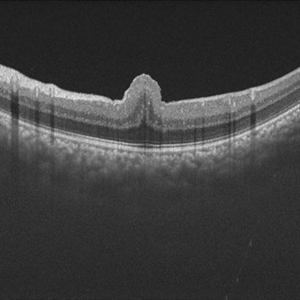

Retinal Fold in Posterior Microphthalmos

Mar 1 2025 by Hemanth Murthy, MBBS, MD, FASRS

Swept source OCT image of Right eye of 34 year male patient with high hypermetropia(+14). BCVA 20/20 in right eye and 20/60 in left eye. Anterior segment was normal. There is loss of foveal pit with omega shaped elevation of inner retinal layers.

Photographer: Mr Veda Vyas

Condition/keywords: posterior microphthalmos